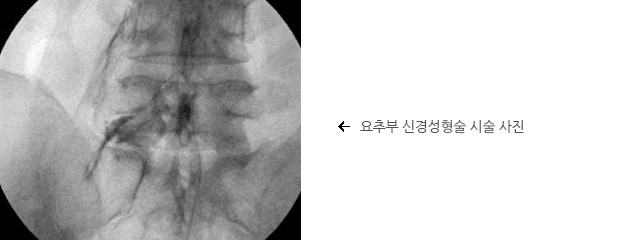

요추부 경막외

신경성형술

신경차단술에 효과가 없는 지속적인 하지 방사통이나 원인이 명확하지 않거나 치료가 어렵고 재발성의 난치성 요통의 경우 요추부위의 신경막 주변주의 유착을 박리하고 신경근의 염증을 가라앉히는 방법으로 천골의 틈새로 접근하여 치료하는 방법으로 수술적 치료 전에 해볼 수 있는 적극적인 시술입니다.

장점은 상처가 없고 시술 후 일상생활이 자유로우며 신경차단술에 비해 효과가 단연 좋지만 단점은 시술비용이 고가이며 시술의 목적이 디스크의 제거가 아닌 디스크 탈출 병변 주변의 유착의 박리와 염증제거인 만큼 시술후의 결과를 완벽하게는 장담할 수 없다는 점입니다.